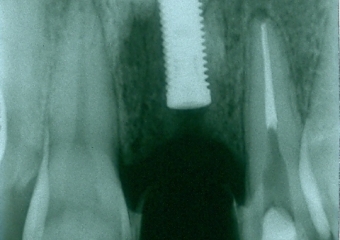

Raio X do implante instalado